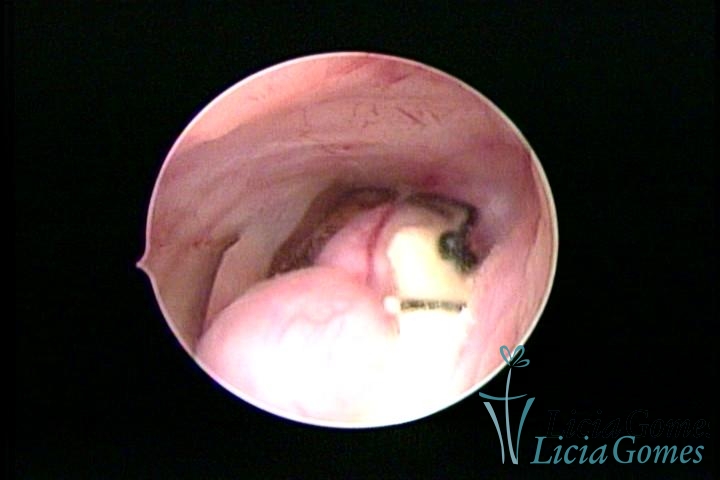

Cicatriz de cesárea com fio de sutura, não absorvido, como corpo estranho

×